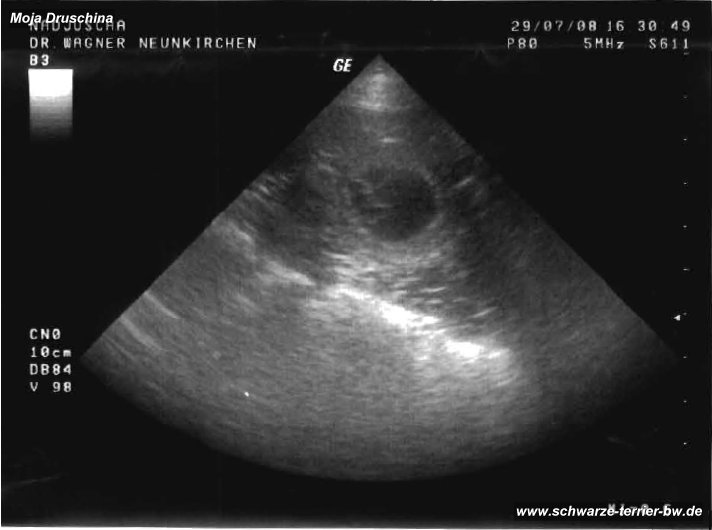

B-Wurf Ultraschall-Bild

Der Anfang....